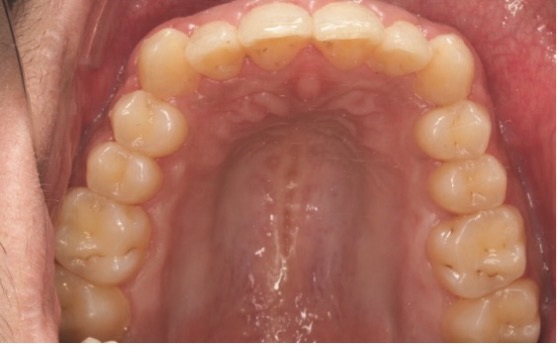

On the 12th visit, 15 months into treatment, an 0.018-by-0.025- inch thermally activated nickel titanium wire (Thermal Ultra) and a 0.017-by-0.025-inch stainless steel archwire (Europa II Genius) were engaged in the upper and lower brackets, respectively. All four maxillary anterior central and lateral incisor brackets were repositioned for a better smile arc, and interproximal reduction from lower canine to canine was performed with energy chain under the brackets to close the spaces with reduced friction. A control panoramic and cephalometric X-ray (Figs. 8a and 8b) were taken at this stage before debonding.